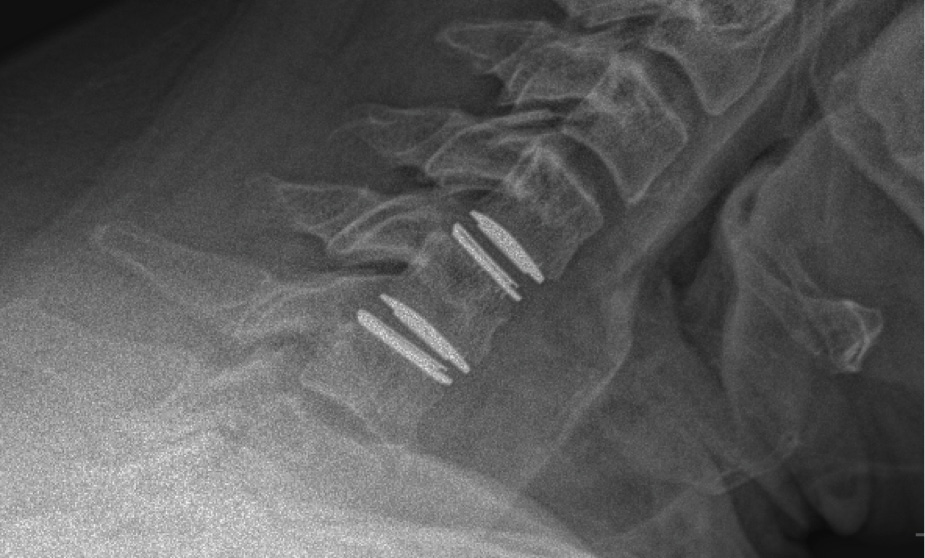

MRIs illustrated mild degenerative disc disease from C4-6 with disc herniations at both C4-5 and C5-6. The axial slice through C4-5 showed a right central disc herniation causing central and mainly right-sided foraminal stenosis. The axial slice through C5-6 showed a central disc herniation also causing central and mainly right-sided foraminal stenosis. The axial slice through C6-7 showed a left-sided disc herniation causing some left-sided foraminal stenosis, however, the patient did not demonstrate any left-sided symptoms.

Upon examination, the patient had good motion on flexion-extension, so fusion was not considered at all. My operative plan was to use prodisc cervical devices and replace both discs at C4-5 and C5-6, giving me the flexibility to use either a domed or flat implant.

During the procedure, prodisc C Vivo fit well within the C4-5 concave endplate. I expected to use a flat endplate prodisc C SK at C5-6, however I trialed the domed prodisc C Vivo and it actually looked good, so I unexpectedly used matching implants.

It was very helpful to have the flexibility to use either a flat or a domed implant at either level. Having the different size options available to truly match patient anatomy that the Match-the-Disc™ System provides enabled me to avoid having to alter the patient’s anatomy to fit the device.